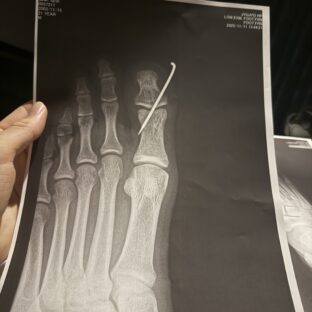

骨折入院

お世話になっております。インストラクターのルイです。 本日は皆様に大切なお知らせがあり、ブログを書かせていただ…